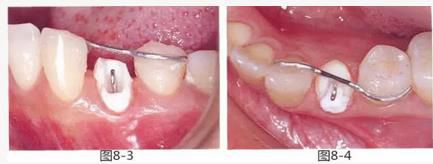

圖8-3 使用方絲和鏈狀橡皮圈,通過正畸的手段挺出牙齒。

圖8-4 使用粘接性樹脂,將S狀方絲固定在鄰牙上。

圖8-5 使用鏈狀橡皮圈進(jìn)行牽引,將S狀方絲與游離牽引鉤之間的距離調(diào)整為2.5mm。